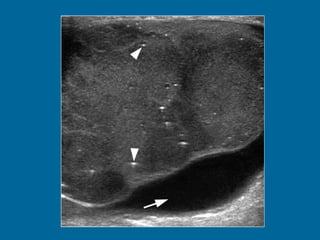

a)  Longitudinal US image of the left testis shows a heterogeneous, predominantly hypoechoic mass, with scattered areas of hypoechogenicity (arrowheads). Normal testicular parenchyma is compressed peripherally by the tumor and contains diffuse microlithiasis (arrow).  (b)  Doppler US image shows normal peripheral vascularity with absence of central flow.

Longitudinal US image of the left testis shows a heterogeneous, predominantly hypoechoic mass, with scattered areas of hypoechogenicity (arrowheads). Normal testicular parenchyma is compressed peripherally by the tumor and contains diffuse microlithiasis (arrow).  (b)  Doppler US image shows normal peripheral vascularity with absence of central flow.

a) LongitudinalUS image of the left testis shows a heterogeneous, predominantly hypoechoic mass, with scattered areas of hypoechogenicity (arrowheads). Normal testicular parenchyma is compressed peripherally by the tumor and contains diffuse microlithiasis (arrow). (b) Doppler US image shows normal peripheral vascularity with absence of central flow.

Longitudinal US imageof the left testis shows a heterogeneous, predominantly hypoechoic mass, with scattered areas of hypoechogenicity (arrowheads). Normal testicular parenchyma is compressed peripherally by the tumor and contains diffuse microlithiasis (arrow). (b) Doppler US image shows normal peripheral vascularity with absence of central flow.